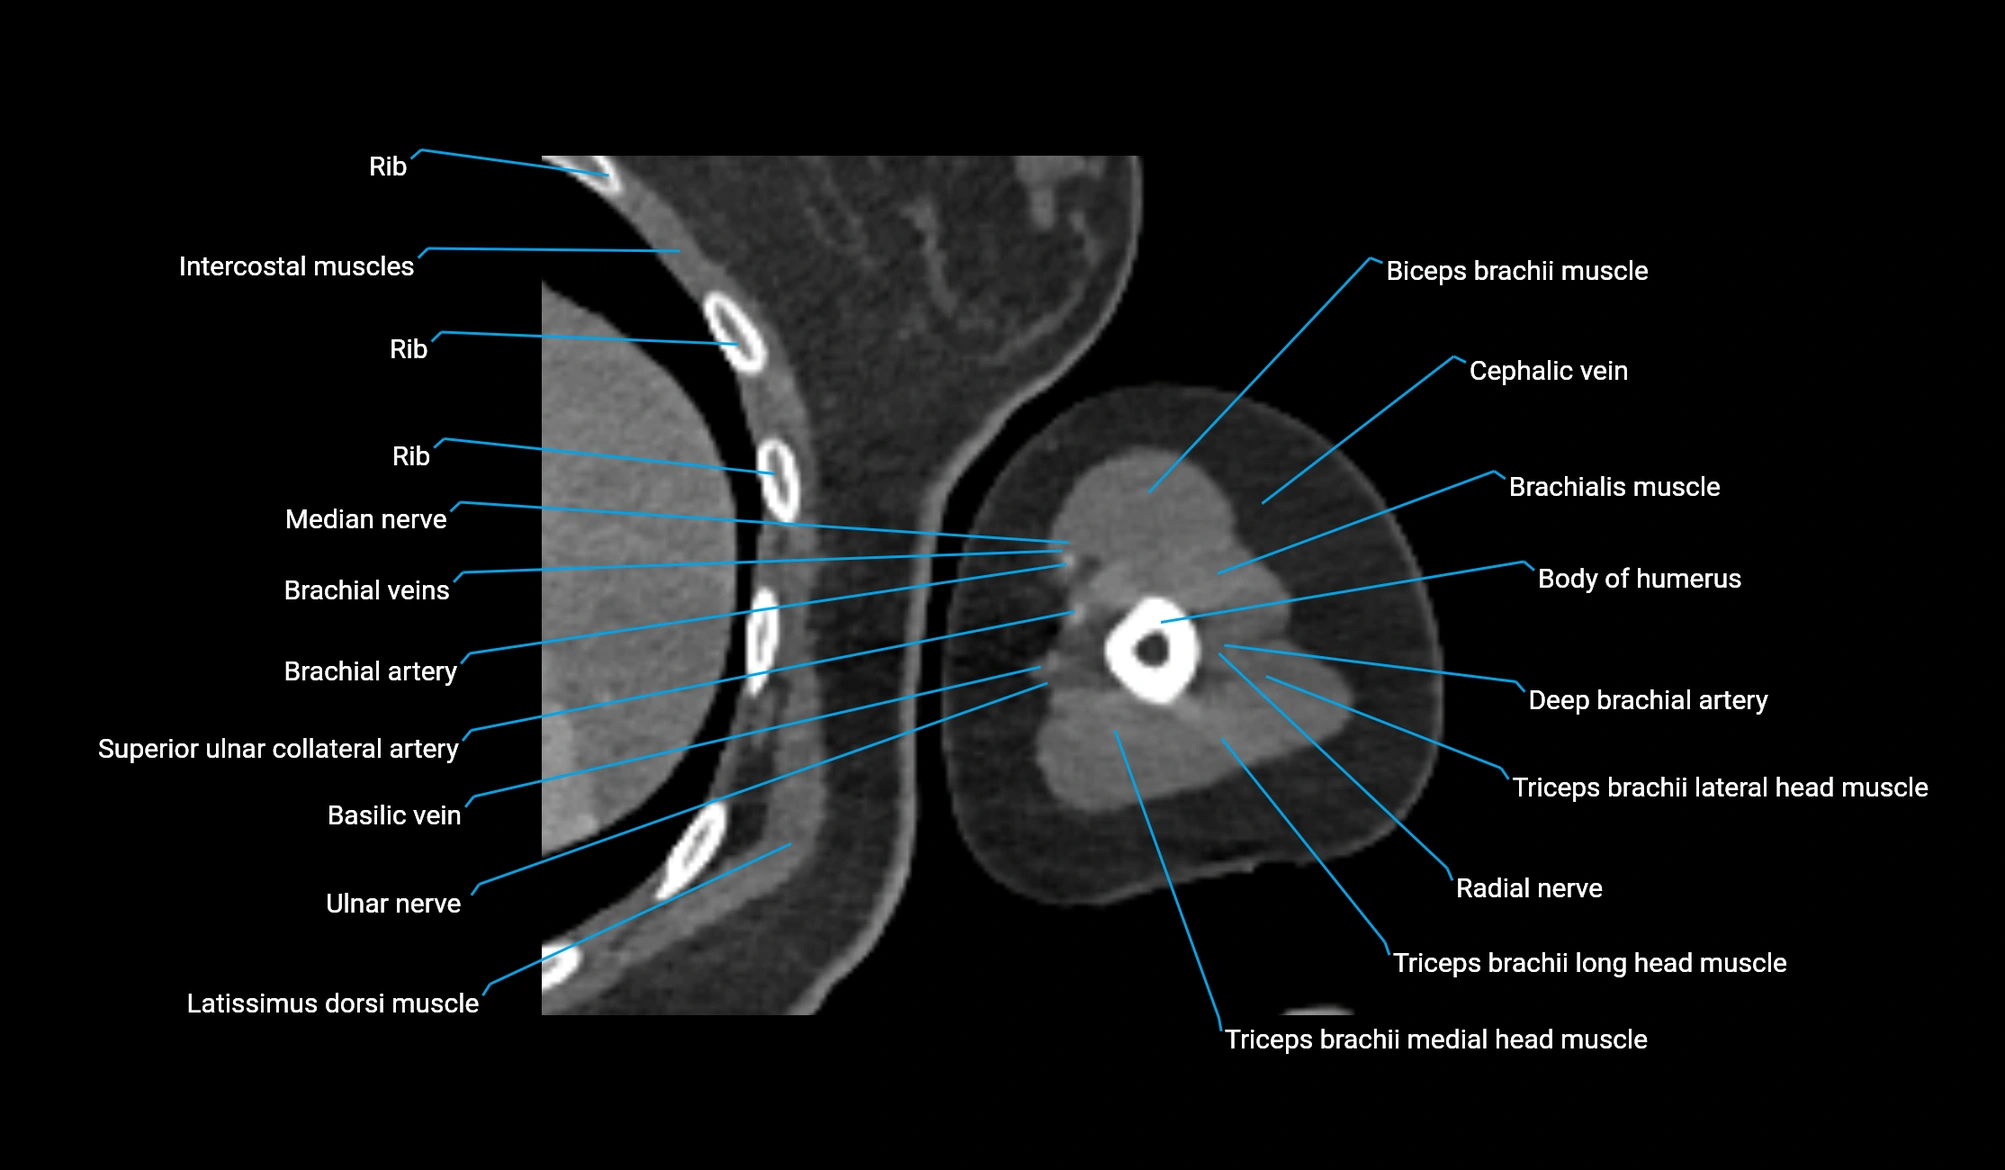

- Body of humerus

- Brachialis muscle

- Cephalic vein

- Deep brachial artery

- Biceps brachii muscle

- Brachial artery

- Median nerve

- Radial nerve

- Superior ulnar collateral artery

- Ulnar nerve

- Lateral head of triceps brachii muscle

- Long head of triceps brachii muscle

- Medial head of triceps brachii muscle